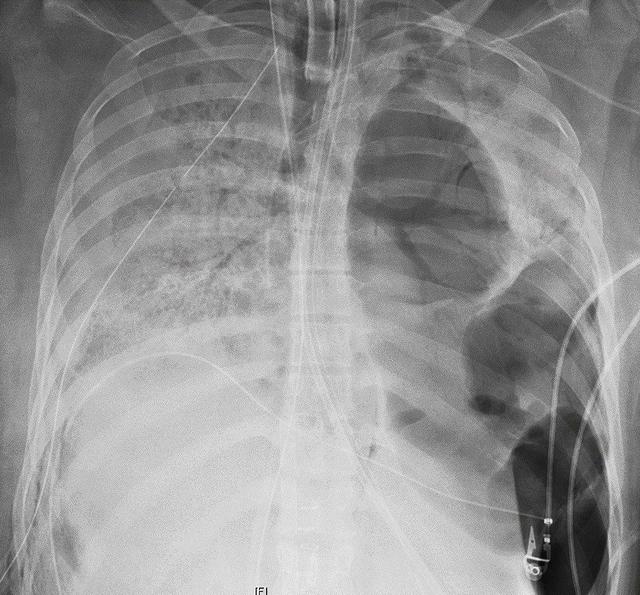

Dr. Ankit Bharat, who performed the surgery, told reporters that the woman — who is in her 20s and had no serious underlying medical conditions prior to contracting COVID-19 — had some of the most damaged lungs he’d ever seen.

The virus had left her lungs full of holes and “completely plastered to tissue around them, the heart, the chest wall and diaphragm,” Bharat told The New York Times.

The disturbing photo on the right shows what coronavirus can do to your lungs.

That lung belonged to a Chicago woman — otherwise healthy and in her 20s — who needed a double lung transplant after battling COVID-19. https://t.co/4nBkHyQdm7 pic.twitter.com/MpjlkTE27q